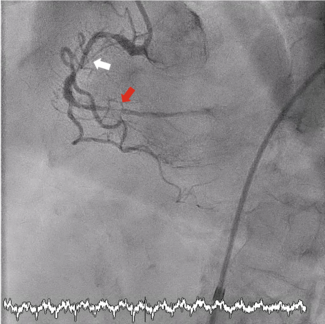

Video 1. Initial angiography showing 99% subocclusive stenosis of the mid-left anterior descending artery and impaired flow.

Video 2. Optical coherence tomography acquisition with high-definition automated analysis (Ultreon software [Abbott]) demonstrating an intact fibrous cap (plaque erosion) and real-time luminal measurements (minimal lumen area: 2.6 mm²) following mechanical reperfusion.